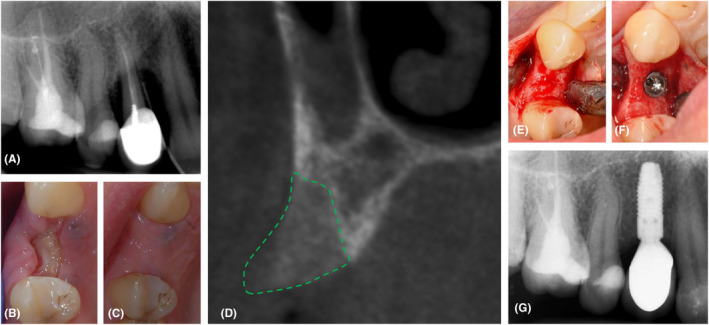

In order to evaluate the therapeutic advantages of various autologous platelet concentrates (APC) as a single biomaterial during alveolar ridge preservation (ARP), a systematic review with meta-analyses was conducted. PubMed, EMBASE, Web of Science, and Scopus were screened for randomized controlled trials (RCTs) that were released prior to 2024. The selected papers compared an APC with either unassisted healing (blood clot) or another biomaterial during ARP (third molars were not included). The outcome parameters included alveolar bone dimension alterations, soft tissue healing, and post-op pain intensity. The search yielded 35 papers (33 studies), one applying platelet-rich plasma (PRP), six using plasma rich in growth factors (PRGF), and 28 using leukocyte- and platelet-rich fibrin (L-PRF). These studies showed a large heterogeneity (e.g., outcome parameters, timing, surgical approach, and inclusion criteria), which hindered drawing strong conclusions. In most studies, however, ARP with PRP, PRGF, and L-PRF alone produced faster soft tissue healing, less post-extraction pain, less alveolar ridge resorption, more socket bone fill, and a higher bone density when compared to unassisted (spontaneous) healing. The ultimate benefit appears to be significantly influenced by the surgical approach. Limited literature exists comparing APC with other biomaterials for ARP, resulting in inconclusive data. APC application for ARP is a promising strategy to improve soft and hard tissue healing and reduce post-extraction pain.